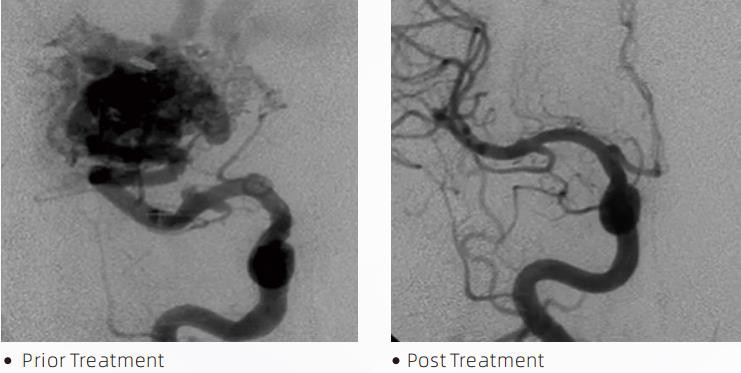

La LavaTMLiquid Embolic System è una terapia endovascolare interventistica per il trattamento delle malformazioni cerebrovascolari. Per malformazione cerebrovascolare si intende un gruppo di anomalie neurovascolari benigne o maligne che possono portare a emorragia intracranica, infarto cerebrale, ischemia cerebrale e altre malattie. Il sistema di embolizzazione liquida è un dispositivo medico somministrato mediante semplice inserimento intravascolare, che embolizza vasi sanguigni cerebrali anomali iniettando uno speciale materiale fluido. Il materiale fluido forma un'embolia tissutale controllata all'interno dei vasi sanguigni, che può ridurre l'impatto delle malformazioni cerebrovascolari sui pazienti. Per accedere al sito di embolizzazione viene utilizzato un microcatetere di rilascio compatibile con DMSO, indicato per l'uso nel sistema neurovascolare. L'agente embolico liquido Lava è un sistema di agente embolico liquido non adesivo composto da copolimero EVOH (etilene vinil alcol) disciolto in DMSO (dimetilsolfossido) e polvere di tantalio micronizzato sospeso per fornire contrasto per la visualizzazione sotto fluoroscopia. LavaTMè disponibile in tre formulazioni di prodotto, LAVA-12, LAVA-18 e LAVA-34. LAVA-12: Consigliato per l'alimentazione di microvasi distali e tramite piccoli alimentatori. LAVA-18: consigliata quando le iniezioni nel peduncolo verranno condotte vicino al nidus; LAVA-34: Consigliato per embolizzare un flusso più elevato e componenti fistolose più grandi.